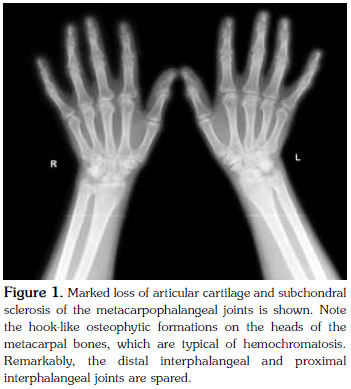

A 44-year-old female patient was admitted to our clinic with complaints of episodic pain, swelling attacks, and progressive deformity in both wrists and metacarpophalangeal joints lasting for five years. Based on her complaints, she had been diagnosed with rheumatoid arthritis and taken methotrexate, sulphasalazine, and prednisolone for two years, however, the patient had discontinued her treatment a year earlier due to ongoing symptoms. Physical examination revealed limited range of motion of both wrists and flexion deformity of the fingers without active inflammation signs. Hand X-ray showed typical signs of osteoarthritis characterized by narrowed joint spaces, subchondral sclerosis, and cyst formation. The distal and proximal interphalangeal joints were markedly preserved, and there were large, hook-like osteophytes in the heads of the metacarpal bones, indicating a typical presentation of hemochromatosis. Laboratory tests revealed that the erythrocyte sedimentation rate and C-reactive protein and uric acid levels were within the normal range, and the antibody tests were negative for rheumatoid factor, anti-nuclear antibodies, and anti-cyclic citrullinated peptides. Although the serum iron and ferritin levels were normal, there was a high transferrin saturation rate. Magnetic resonance imaging demonstrated a hepatic iron concentration of 44 μmol/g (reference: <36 μmol/g). Genetic studies showed homozygous for the H63D mutation. Based on these findings, the patient was diagnosed with hereditary hemochromatosis and scheduled for follow-up visits. In conclusion, hemochromatosis should be considered in the differential diagnosis in patients suffering from slow-progressing arthritis with chronic deformity.

A physical examination revealed decreased ROM in both wrists and the MCP joints with accompanying flexion deformities; however, the affected joints did not demonstrate any signs of active inflammation. Furthermore, the patient's hip joint movements were painful and restricted. Typical signs of osteoarthritis (OA) (irregular narrowing of joint spaces, subchondral sclerosis, and sclerotic cyst formation) were seen on hand radiograms (Figure 1). Strikingly, the distal interphalangeal (DIP) and PIP joints were intact, and hook-like osteophytic formations on the heads of the metacarpal bones were seen, which is typical of hemochromatosis. Pelvic radiograms revealed irregular joint space narrowing, sclerotic changes, and subchondral cysts involving the hip joints (Figure 2). Additionally, the laboratory findings showed a normal erythrocyte sedimentation rate (ESR) and C-reactive protein (CRP) levels, and the patient tested negative for rheumatoid factor (RF) as well as anti-cyclic citrullinated peptide (anti-CCP) and antinuclear antibodies (ANA). Furthermore, the serum uric acid level was normal, and the liver function test results were within normal limits. Although the serum iron and ferritin levels were also within normal limits, the transferrin saturation rate was higher (69.71%) than normal (<55%). Moreover, the patient's estimated hepatic iron concentration was 44±20 μmol/g (normal <36 μmol/g) using T2 sequences in abdominal magnetic resonance imaging (MRI). A genetic examination also determined the existence of a homozygous H63D mutation; therefore, the patient was diagnosed with HH based on the clinical, radiological, and laboratory findings.

In the majority of cases, arthropathy is seen in advanced stages, but it can be the first sign in the iron accumulation process.[6] However, it is unrelated to the iron load in the body. Involvement of the wrists along with the MCP (mainly the second and third digits), and PIP joints, which mimicks OA, are the most characteristic findings, but the preservation of the DIP joints is important in order to discriminate the arthropathy from primary OA. New, hook-like bone formations on the heads of the metacarpal bones are critical radiological signs that signal the presence of HH.[7-9] In our patient, the clinical and radiological characteristics of joint involvement supported our diagnosis of HH.

Short-lived acute inflammatory episodes triggered by calcium pyrophosphate crystals can mimic RA,[9,10] but our radiographic and laboratory findings ruled out this diagnosis. Testing for anti-CCP antibodies and RF is useful to help discriminate HH from RA. In our case, the conjunction of negative RF and anti-CCP tests made this diagnosis unlikely. Additionally, the ESR and CRP levels were normal, and the presence of characteristic radiological findings, including metacarpal osteophytes and subchondral sclerosis, was consistent with HH since those are usually not seen in patients with RA. Typical radiographic findings of RA include periarticular osteopenia and marginal erosions.